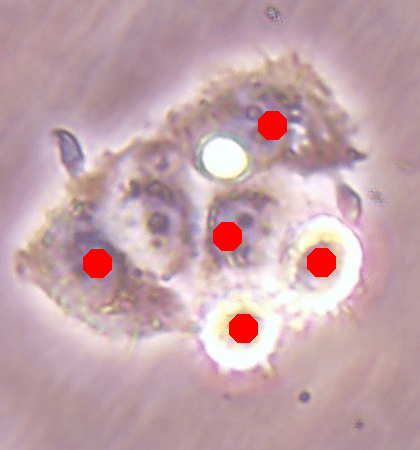

![]() |

| (a) | (b) |

| (c) | (d) |

For an example subimage given in Fig. 2a, these distance definitions are illustrated in Figs. 2b and 2c, respectively. The inner distance definition well indicates the cell centers since it uses the Euclidean distances from pixels to their closest cell centers. However, as it uses the centers as the reference point, the distance decrease from a center to its boundaries is the same for all directions and for all cells. Thus, when it is used alone, this definition imposes a circular and one-sized shape on the cells, as also seen in Fig. 2b. On the contrary, since the normalized outer distance is calculated with a reference to a cell boundary, this decrease may differ from one direction to another as well as from one cell to another, depending on the shape and size of the cell. Thus, it better preserves the morphological characteristics of cells, as seen in Fig. 2c.

The proposed DeepDistance model considers cell detection as a multi-task regression problem that estimates two distance maps from the RGB image, one for formulating the main task of cell detection and the other as an auxiliary task with the motivation of more effectively learning the main task. The FCN architecture given in the previous section is designed to learn these two regression tasks at the same time. This section discusses how this model can be extended to cover more auxiliary tasks, concurrent learning of which may further increase the performance of the main task. For this purpose, this section implements an extended version of the DeepDistance model that comprises an additional task of cell pixel classification. This additional task aims to construct a classification map (as shown in Fig. 2d) from the shared features of the encoder path111To take overlapping cells apart, and hence to obtain an improved map, cell boundaries are widen and subtracted from the classification map. This improved map is also used in the comparison methods to make fair comparisons.. Note that here, instead of defining another regression problem as the additional task, we use a classification problem in order to demonstrate that the model can easily be extended to cover the auxiliary tasks related with regression as well as classification.